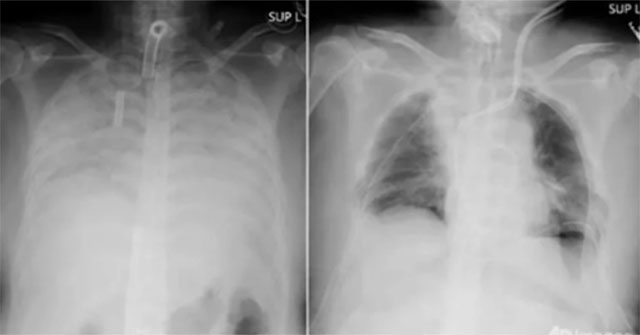

Hội chứng phổi trắng (thường được mọi người gọi là bệnh phổi trắng hay phổi khô) là chỉ tình trạng phổi có màu trắng xoá trên phim chụp X quang.

Chụp X quang phổi là một kỹ thuật quen thuộc trong y khoa. Máy chụp X quang sẽ phát ra những chùm tia X bức xạ cao xuyên qua các cơ quan, dựa trên mức độ hấp thụ và phản hồi của tia X mà cho ra hình ảnh các cơ quan như: phổi, tim, mạch máu,.. trên phim X quang. Các cơ quan, tổ chức bên trong lồng ngực sẽ hiển thị trên phim X quang với các màu sắc trắng, xám, đen với mức độ đậm nhạt khác nhau.

Bình thường, một lá phổi khỏe mạnh khi chụp phim X-quang, thì sẽ thấy phổi trong (hình ảnh hiển thị máu đen). Tuy nhiên, do viêm phổi hoặc bệnh lý khác dẫn đến phim phổi có hình ảnh trắng bất thường.

Hình ảnh X-quang phổi trắng. (Ảnh minh họa).